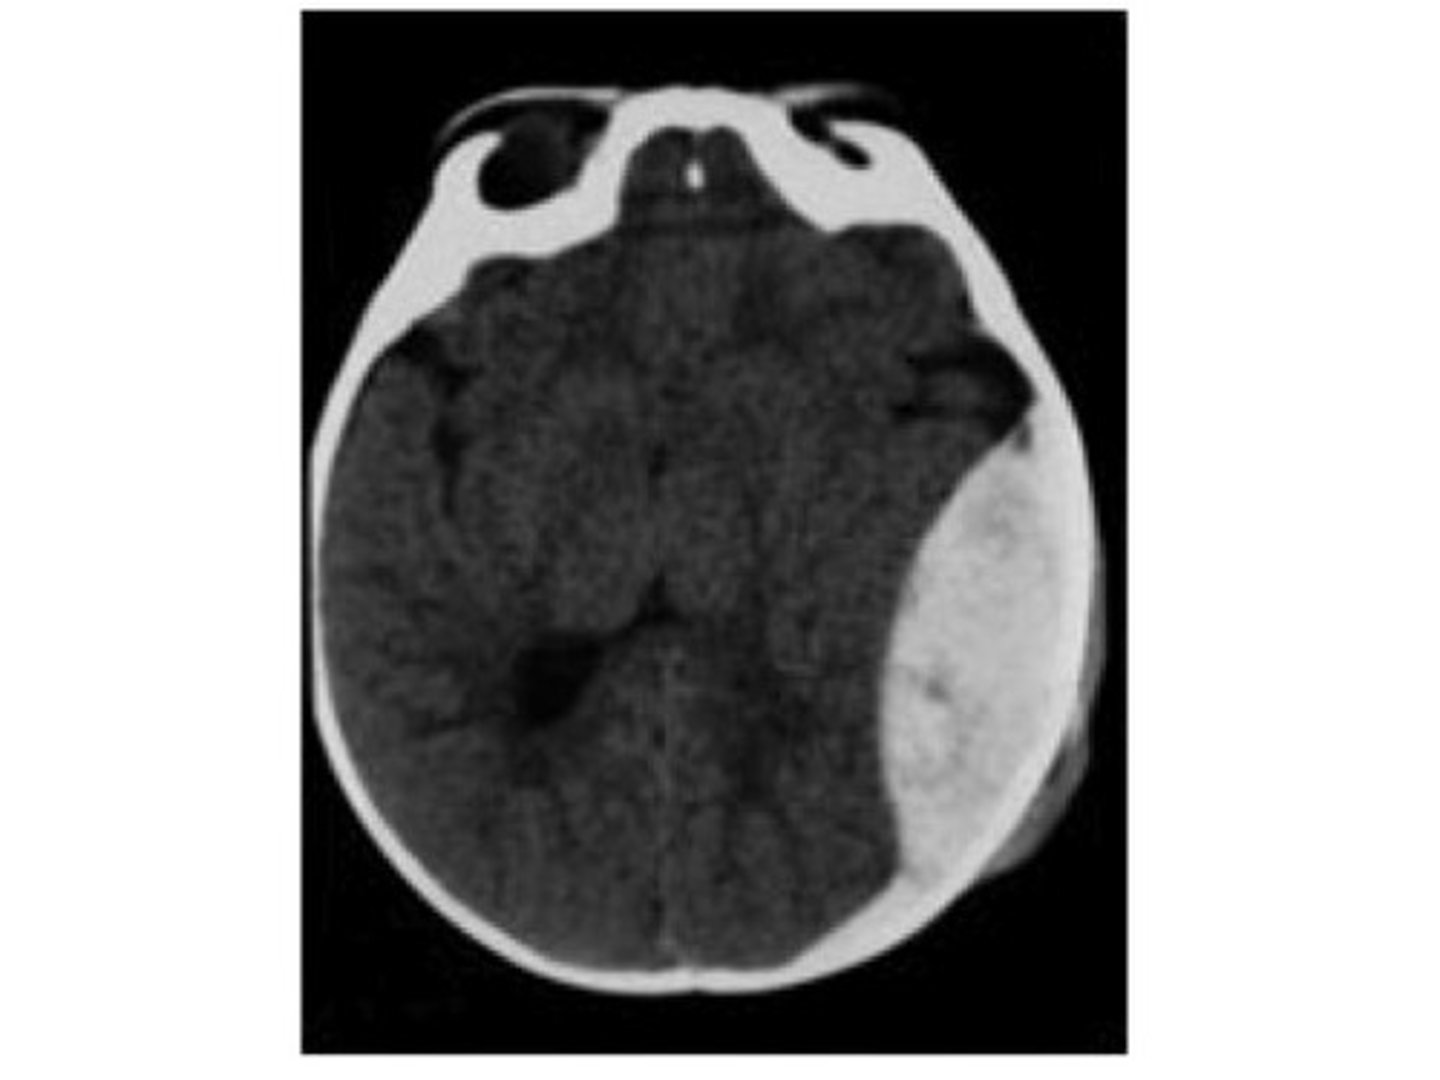

Epidural hematoma

accumulation of blood (meningeal artery) between dura and skull that is from trauma with a biconcave lens shape on CT

Subdural hematoma

accumulation of blood (bridging veins) between dura and arachnoid mater that is from acute or chronic occurrences with a crescent-shape on CT